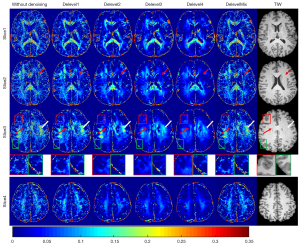

The comparison of four slices of MWF images based on a randomly picked raw dataset (noise level =0.0197, corresponding to Level3), before and after denoising using the five MCDnCNN models showed that there was substantial random variation in MWF maps derived from the noisy images, as well as artifacts known as “voids” (voxels with very low-MWF values), as indicated by the red rectangle and red arrow in Slice3 and red arrow in Slice2 (Figure 5). After denoising by the MCDnCNN models, the MWF values appeared to have removed most of the artifacts, with those random variations removed and even the voids filled (Figure 5, Slice3 and Slice2, Delevel3). In contrast, the MCDnCNN models were also able to adjust those extraordinarily high MWF values to more appropriate ones (Figure 5, white arrow in Slice3). Moreover, the MWF maps calculated from the MCDnCNN-denoised images exhibited preservation of edges and small structures (Figure 5, green rectangle in Slice3). The results also demonstrated that all the 5 denoising models unanimously reduced random variation although the level of reduction was different. In addition, the MWF values obtained from the noisy images were generally higher than those obtained from the denoised images. The computation times required to denoise the entire dataset using MCDnCNN was about 25 s.

The MWF values derived from the denoised in vivo data treated by the MCDnCNN models agreed well with the results derived from the data in the simulation experiments, whenever an appropriate denoising model was applied in accordance with the noise level of the corresponding dataset. It infers that to avoid overestimating or underestimating MWF in the in vivo data, we must first estimate the noise level of the data, and then particularly choose the Delevel model that is appropriate for the noise level of the data. In Figure 5, we see that using an appropriate MCDnCNN model (i.e., Delevel3) may improve the quality of MWF mapping, including filling the voids, reducing over-estimation and preserving structural details. Although the void (red rectangle in Slice3; Figure 5) was at the boundary of white matter adjacent to neighboring gray matter, which is visible better in T1-weighted image of the same subject, myelin component was expected. Similar but more convincing evidence is presented at the tips of the red arrows in Figure 5 on both Slice2 and Slice3. The areas pointed by the white arrow in Slice3 contained lots of myelinated fiber bundles. However, most of these fibers were approximately parallel or perpendicular to the B0 direction in our case (B0 was perpendicular to the axial plane in Figure 5). Previous studies reported that the angle between the myelination fiber bundles and the B0 direction will affect the accuracy of estimating MWF (9,10,12), just like what we have seen in our experiments using the simulated data. In line with the findings in these papers, the myelin components in the fiber bundles that were either parallel or perpendicular to the B0 direction would achieve lower SD in estimating the MWF values. According to the latest research, the MWF value range in this portion of the fiber bundles in the brain is about 9–15% (43), and our results of the data before denoising were obviously higher while the results of the data after denoising by Delevel3 were consistent with the reported in the literature. Therefore, we reasonably believe that our results showed an improvement of accuracy in MWF estimation.

In contrast, the other four denoising models (Delevel1, Delevel2, Delevel4 and DelevelMix) performed poorly. For example, the same data denoised by the four models failed to estimate meaningful MWF values to fill the voids (Figure 5, areas at the red arrows in both Slice2 and Slice3). And in some areas, data denoised by Delevel1, Delevel2 and DelevelMix resulted in MWF values that were obviously too higher than the reported range (Figure 5, areas indicated by the white arrows), while data denoised by Delevel4 resulted in MWF values that were obviously lower than the reported range (Figure 5). Moreover, extreme results appeared in the ROI analysis of the data denoised by Delevel1 and DelevelMix that, for example, the mean of MWF values in the forceps minor were overly higher than those derived from original data, which were already higher than the reported results (Table 4) (12,35). Thus, the inappropriate models led to denoised data that turned out either an over- or an under-estimation of MWF values.

Checking against the corresponding T1-weighted image (last row, Figure 5) in which the structural boundaries are more intuitive, we may see that the small structural details in white matter were well preserved in the data denoised by Delevel3 (Figure 5, green rectangle in Slice3). Yet, we noticed that some structures, such as the genu in the frontal lobe, disappeared in the results based on the data denoised by the MCDnCNN models. The disappearance here was also observed in data of high SNR acquired using an ultra-high field strength at 7 T (10). In fact, investigators speculated that such disappearance is not caused by denoising but is related to B0 inhomogeneity (8,17). Our main purpose in the current work was to study the benefits of employing appropriately denoised data in MWF estimation, however, denoising cannot correct artifacts caused by B0 inhomogeneity. The experiments have shown that the mean values of the calculated MWF values based on data denoised using the appropriate models were generally in good agreement with those previously reported in the literature (Table 4). However, the SD values of the MWF, especially in the genu of corpus callosum, were slightly higher than those reported, although they were still within the acceptable range according to Alonso-Ortiz’s report (44). We speculate that this phenomenon was due to a higher spatial resolution, and thereby a reduced SNR and inherently the aforementioned issue of ill-conditioned problem. Further experiments and analyses would be necessary to double check this speculation.